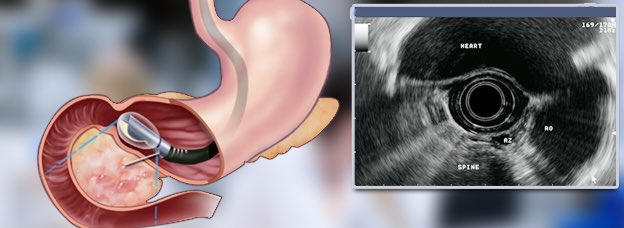

يتم فحص هذه التغيرات عن طريق التنظير الصوتي للورم.

في الأورام التي لا تصاحبها اعراض و يقل حجمها عن ٢ سم و لا تتوفر فيها اي من مظاهر التحول السرطاني، يتم متابعتها بصفة دورية لدى طبيب الجهاز الهضمي في مراكز تتوفر فيها الفحص بالتنظير الصوتي.